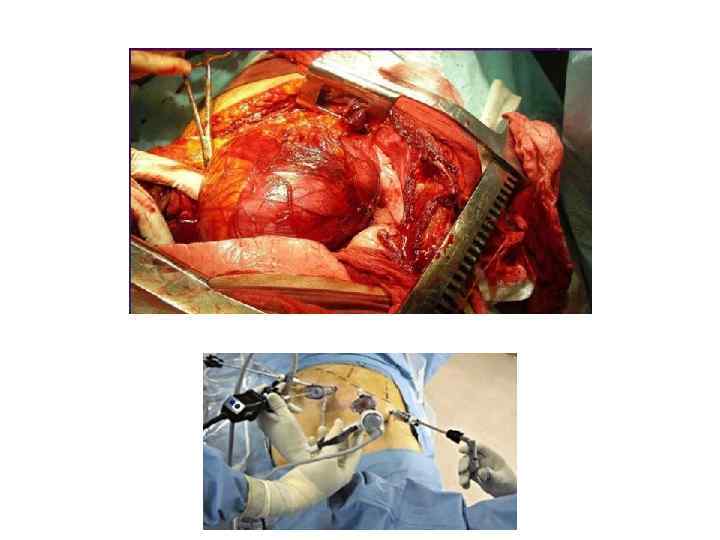

Лечение • Хирургическое лечение (гормональная активность, размеры > 6 см, АКР) • Динамическое наблюдение (КТ через 6, 12, 24 месяцев после первичного выявления) • Исключение гормональной активности – не менее 4 лет после первичного выявления «Эндокринная хирургия» / Под ред. Дедова И. И. , Кузнецова Н. С. , Мельниченко Г. А. – М. : Литтерра, 2011